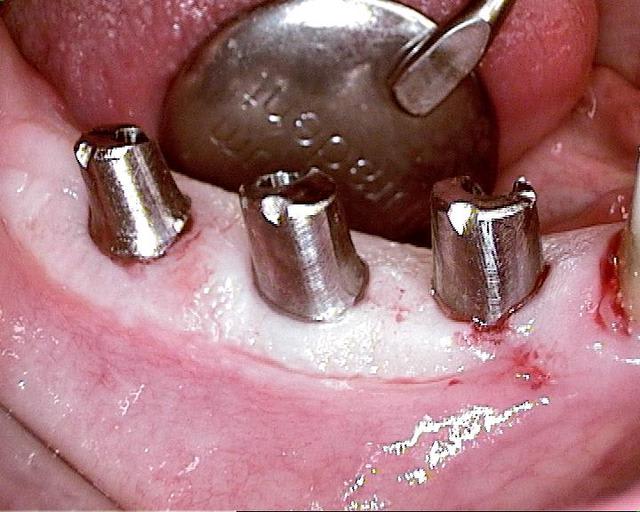

Pour ceux que ca interessent, et parce qu on a m a demandé des cas supplémentaires dans le sujet 23 implants rehabilitation totale, voici un autre cas d implantation immédiate avec la technique minimalement invasive et condensation grace aux forets.

Le patient a reçu un traitement il y a dix ans dans le maxillaire et dans le 4eme quadrant.Comme on peut le voir j´ai du extraire quelques dents au maxillaire: 35 37 et 45.

Le septum de la 37 a été foré avec un foret conique 3 faces.

J ai planté à 60 Ncm sans fracturer le septum.Juste après l opération , les prep caps en zircon ont été cémenté.La restauration définitive 34 jusqu` à 37 été fixé 2 semaines après l implantation avec implantlink (detax). Après un an, le bridge a été retiré facilement pour voir l´état de la gencive et faire une radio de contrôle.On la re ossifiction est satisfaisante et que la gencive "aime" le zircon.

Le bridge a ensuite été recémenté sans correction nécessaire du bridge.